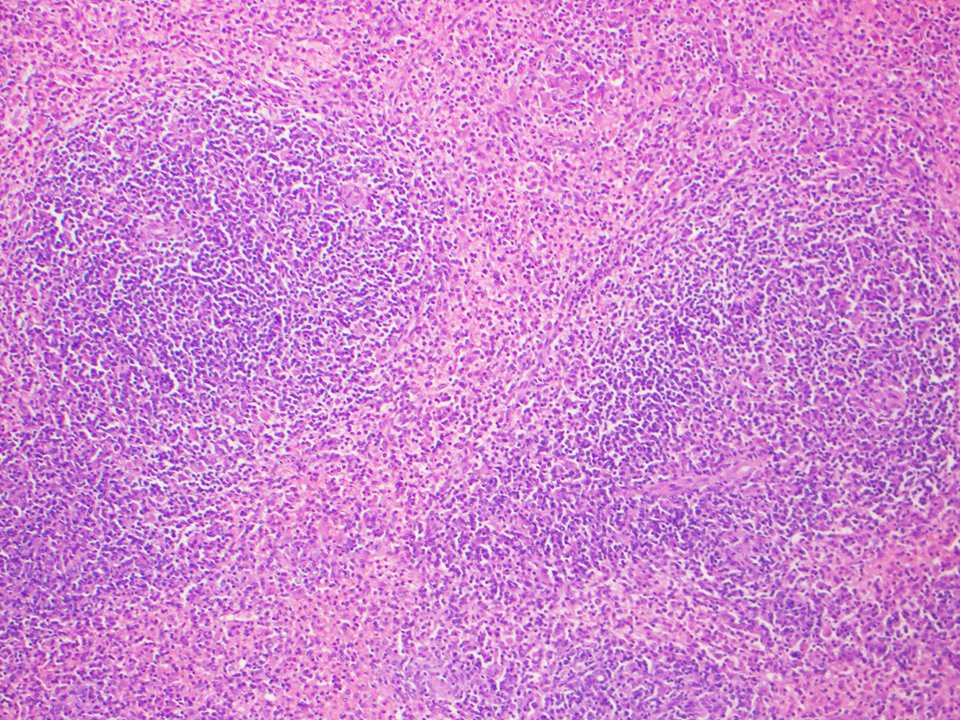

An example of splenic marginal zone lymphoma (SMZL): Infiltration of the red and white pulp by neoplastic small B-cells,highlighted by CD20.Epithelioid histiocytes may be seen in the lymphoid aggregates in SMZL, as shown in this case

#Hemepath#lymsm#spleen#endcancer#surgpathpic.twitter.com/kx1eUdmX5I